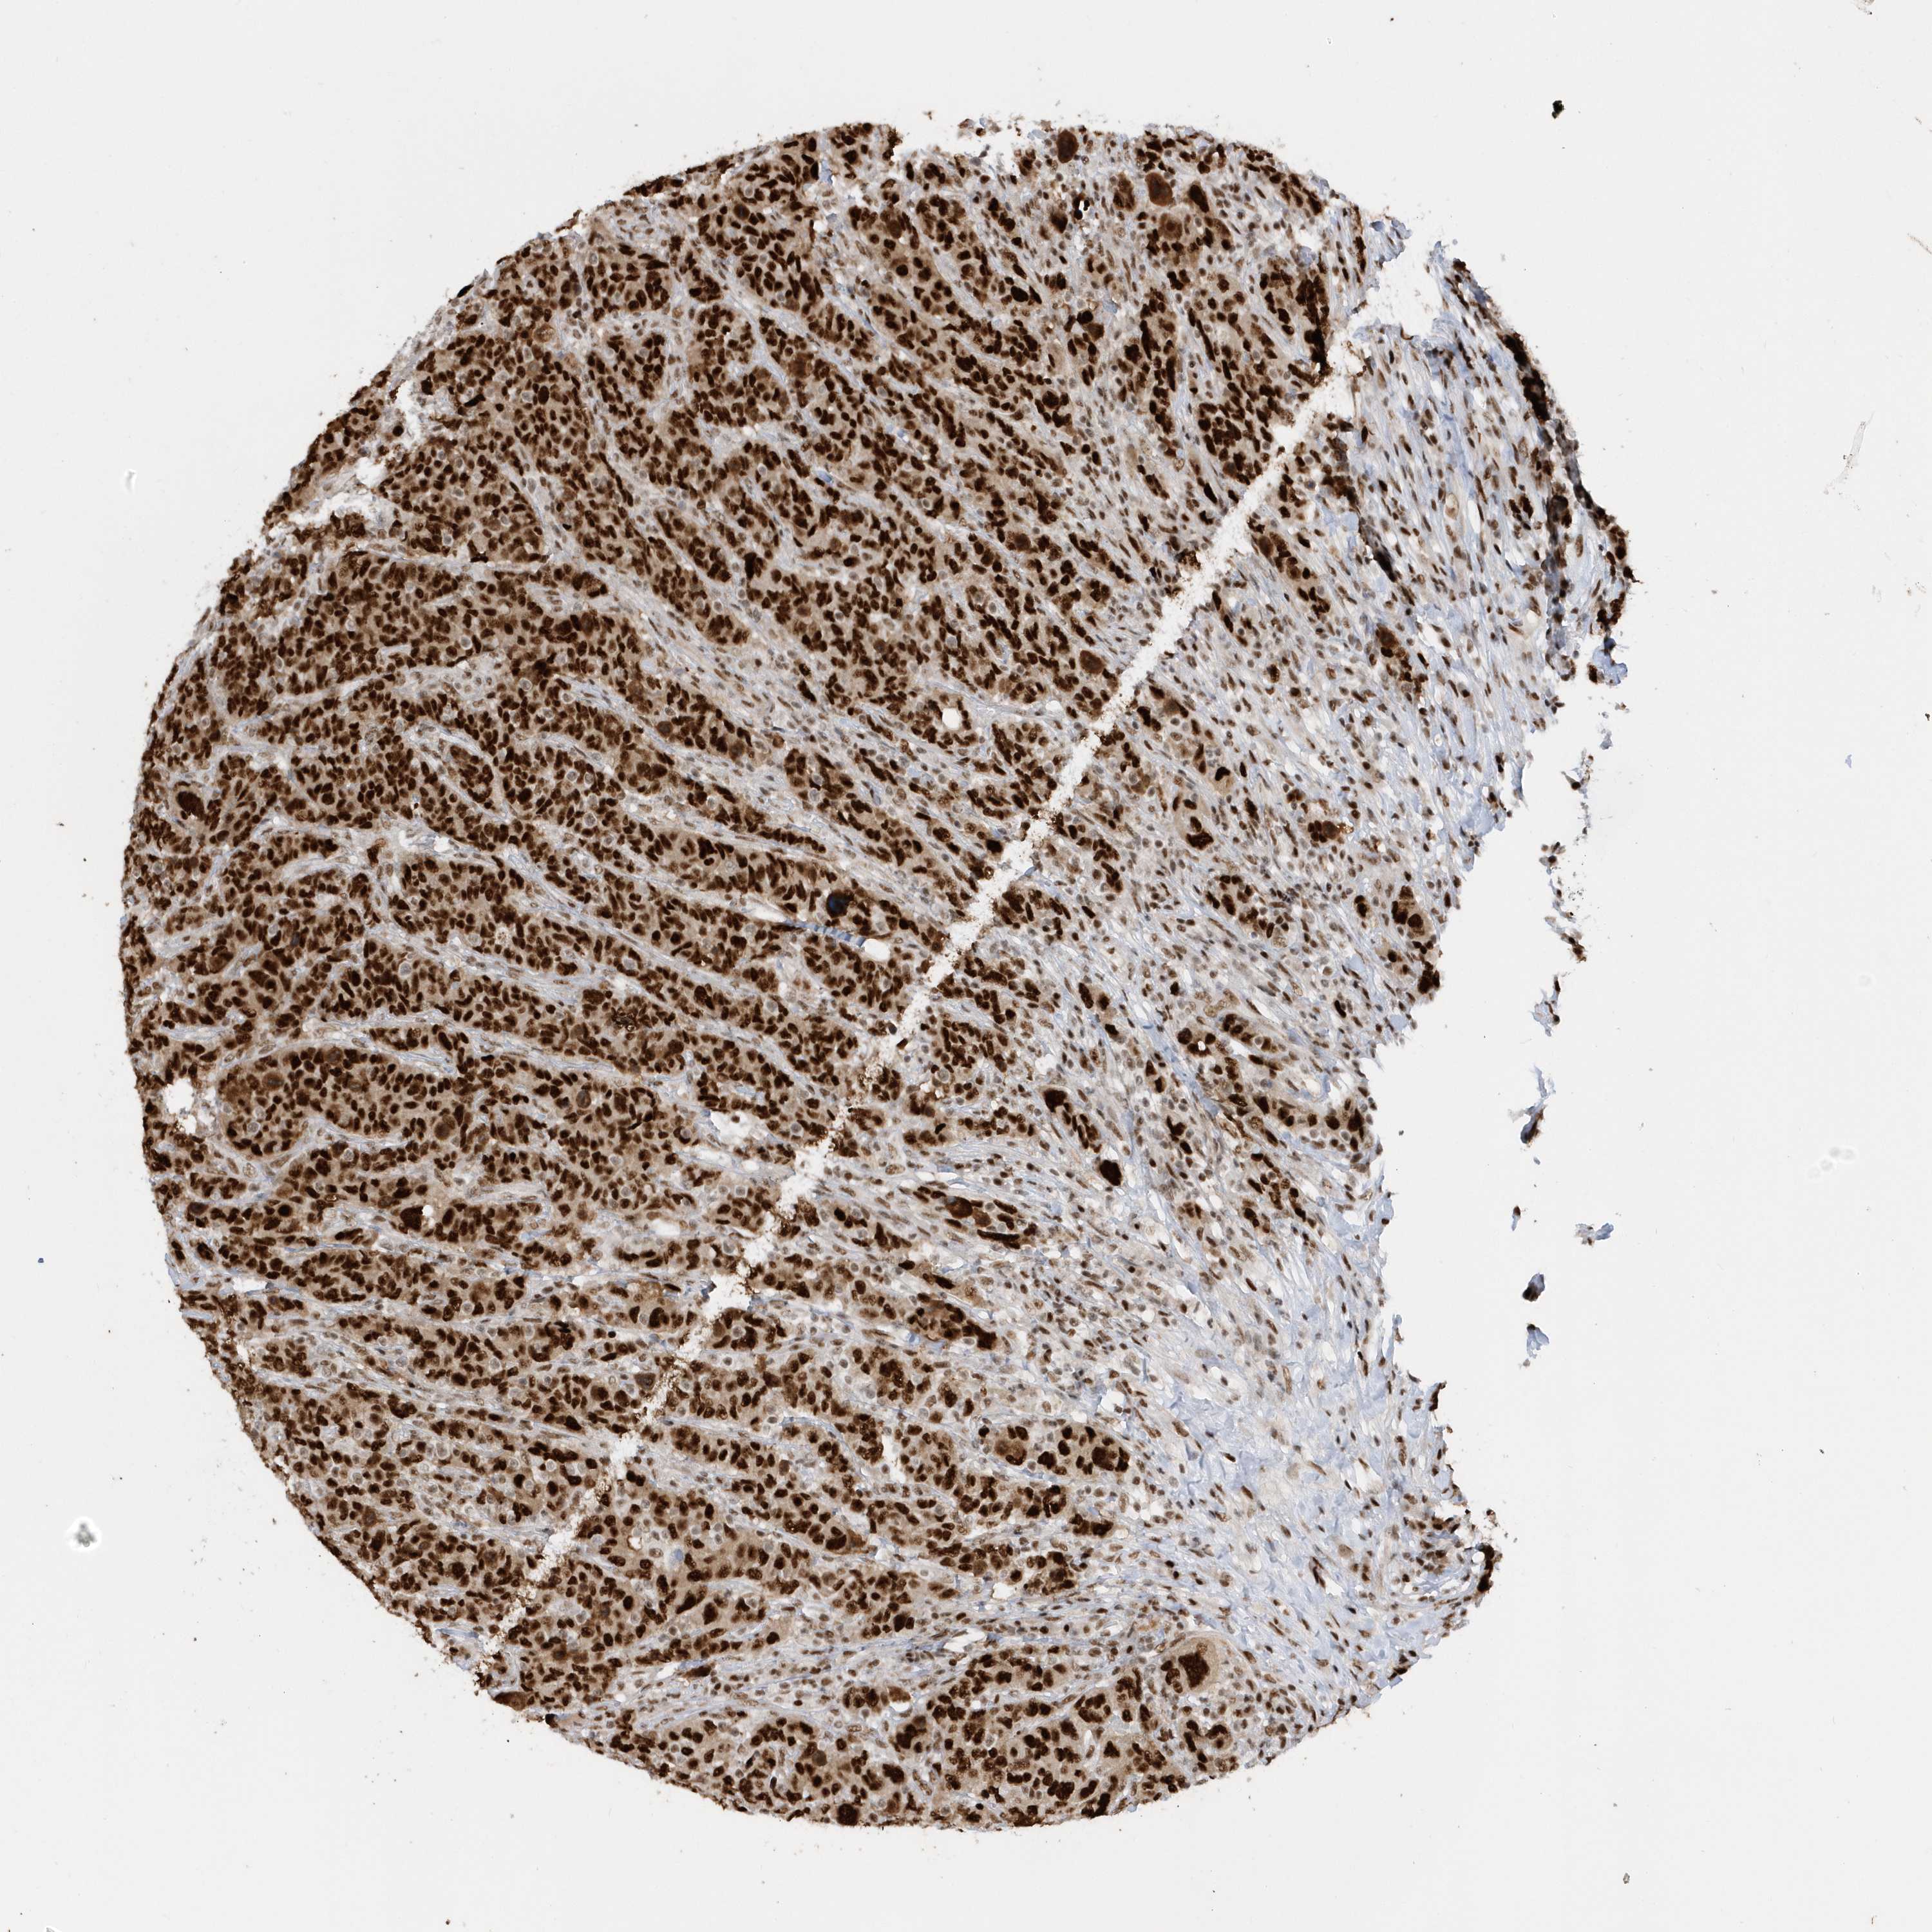

CANCER BREAST CANCER Show tissue menu

BRCA TCGA BRCA VALIDATION PROTEIN EXPRESSION